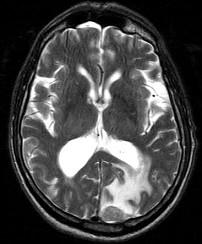

问题 男,77岁,胃癌术后2年,头痛1月,请结合影像图像选择最可能的诊断()

选项 A.脑脓肿 B.松果体瘤 C.神经胶质瘤 D.胃癌脑转移 E.脑膜炎

答案 D